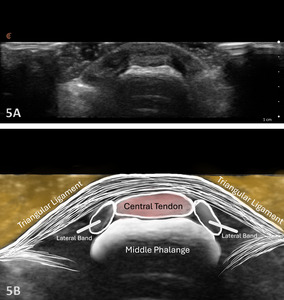

Examination Protocol Normal Sonographic Appearance

The extensor tendon can be examined in both long axis (LAX) and short axis (SAX) views. The tendons can each be seen at the MCP and PIP joints. The hyperechoic outline of the metacarpal and proximal phalanx will be seen at the MCP joint, while the proximal phalanx and middle phalanx will be visualized at the PIP joint. The extensor tendon will be an echogenic fibrillar structure in appearance. In the LAX view, the tendons will become smaller as they run more distally, making them slightly more difficult to visualize. In the SAX view, the tendon should be oval and fibular and should sit in the central position over the metacarpal. The soundhead may need to be toggled at the distal tendons’ insertion to avoid anisotropy. Dynamic visualization can be performed with resisted or active movement of the wrist or fingers.